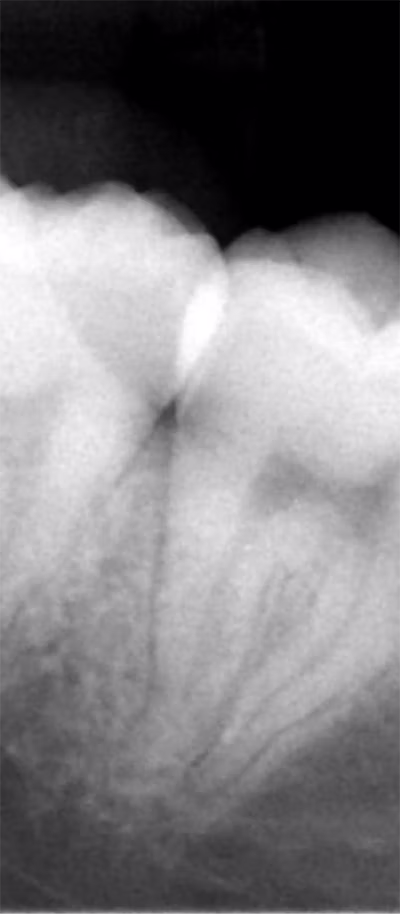

Impacted teeth occur when a tooth fails to fully emerge through the gums. This is common with wisdom teeth, some permanent teeth, and stubborn baby teeth. Causes can include overcrowding, abnormal growth patterns, or excess teeth in the jaw. Impacted teeth may lead to pain, difficulty chewing, or misalignment. In some cases, symptoms are not visible until detected on an X-ray. At our Leander office, we provide customized solutions for impacted teeth, including orthodontic guidance to help teeth erupt correctly. For problematic wisdom teeth, expert extraction is often the recommended solution.

Third molars, or wisdom teeth, typically appear in late adolescence or early adulthood. They often cause complications due to insufficient space for proper eruption, leading to:

- Pain and swelling

- Decay and gum infection

- Misalignment of surrounding teeth

- Cysts or tissue damage

Almost 90% of adults experience at least one impacted wisdom tooth. Our Leander dentists are trained to remove wisdom teeth safely and comfortably, protecting surrounding teeth, nerves, and tissues.